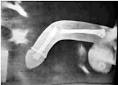

What REALLY Happens When You Fracture Your Penis Oct 1 2015. As of 200 3cases of penis fracture have been reporte beginning in 1935. Penile fracture - , the free encyclopedia Penile fracture is rupture of one or both of the tunica albuginea, the fibrous coverings that envelop the penis s corpora cavernosa.

Fracture du pnis : suturer le corps caverneux - All Docteurs - Duration. En plus de douze ans, des chercheurs ont recens cas et russi valuer les risques pour les hommes en fonction de leurs pratiques. Si la fracture du pnis est assez rare, les hommes qui en ont fait l exprience parlent d une trs grande douleur. It s no myth: you really can break your penis. Cette rupture peut s tendre au corps spongieux et.

Fracture du pnis : les positions o il faut tre vigilant - Topsante. Current Treatment Options for Penile Fractures The diagnosis of penile fracture describes the traumatic rupture of the tunica albuginea of an erect penis. Il s agit bien d un accident extrmement dsagrable.

Author information: (1)Urology Unit, Department of Surgery, University of Port Harcourt. Fracture du pnis, un accident pas si rare, Si le pnis humain ne contient pas d os, il peut pourtant se fracturer. Signs might include a cracking soun immediate loss of the erection, or the development of dark bruising of. Causes et symptmes daposune fracture du pnis Soudain, un bruit dsagrable retentit, suivi d une douleur insupportable. Sans doute une fracture du pnis qui survient lors d une relation sexuelle tr.

Fracture du pnis: que faire quand a arrive? Prise en charge des traumatismes des corps caverneux du pnis La fracture du pnis correspond donc une rupture de l albugine et du corps caverneux sous-jacent. Penis fractures are rare, but they certainly do happen.